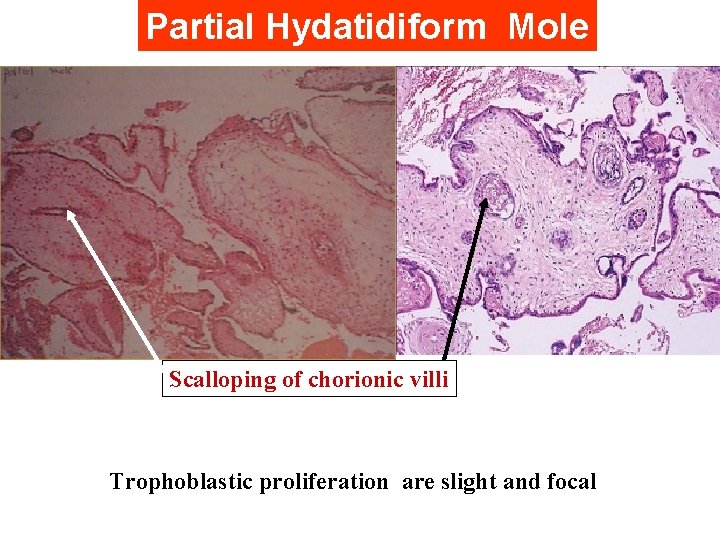

Partial H. Mole Microscopically: The enlarged, edematous villi and abnormal trophoblastic proliferation are slight and focal and did not involve the entire villi. There is a scalloping of chorionic villi Fetal or embryonic or fetal RBCs Macroscopically: The molar pattern did not involve the entire placenta. Uterine enlargement in excess of gestational age is uncommon. Theca-lutein cysts are rare Fetal or embryonic tissue or amnion

Partial Hydatidiform Mole Scalloping of chorionic villi Trophoblastic proliferation are slight and focal